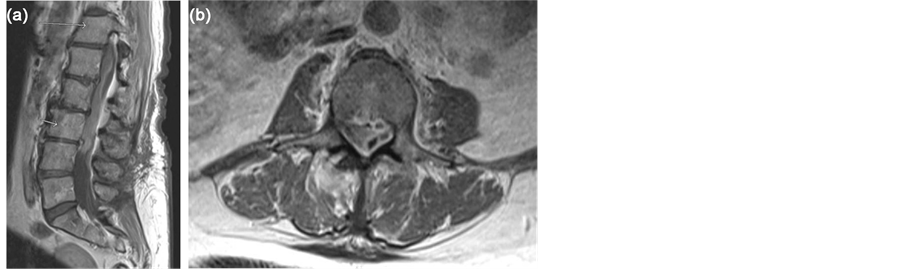

A healthy 65-year-old female presented with axial back pain, paraparesis, paresthesias, myelopathy, and a mild leukocytosis after being hospitalized with community acquired pneumonia 2 weeks prior. She underwent L3-5 laminectomy 7 months prior without a dural tear. MRI revealed a SSE from T8 to L4. The patient underwent emergent T10-L3 laminectomy with dural opening, exploration, and washout of the SSE. Intra-operative cultures grew Streptococcus agalactiae. The patient was treated with intravenous ceftriaxone and made a full recovery at 6 months post-operatively (Figures 1-3).

Figure 1. (a) Pre-operative sagittal T-1 weighted post-contrast MRI of the lumbar spine shows diffuse subdural collection with no evidence of epidural extension. (b) Pre-opera- tive axial T-1 weighted post-contrast MRI of the L3 vertebral body level shows loculated subdural collection effacing the thecal sac.